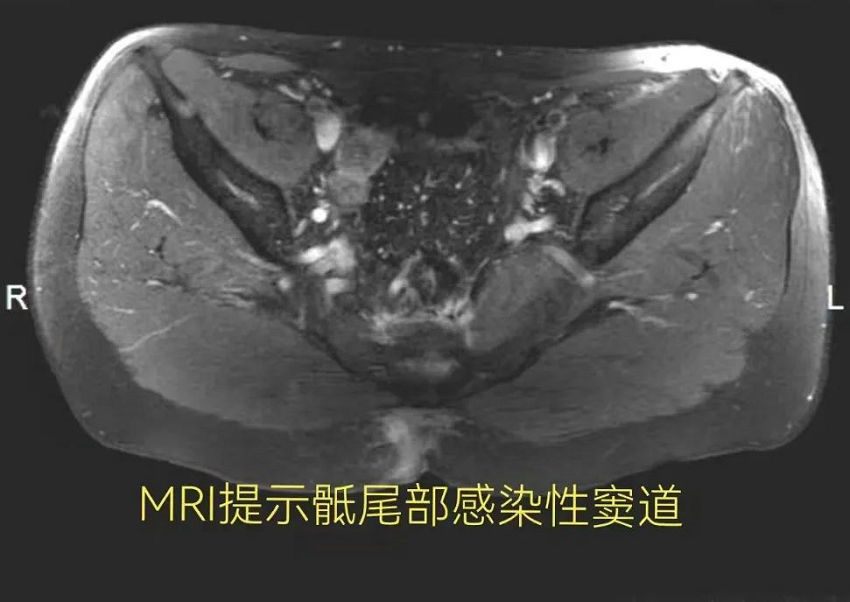

胃肠甲状腺外科罗医生接诊患者后,结合患者的就诊经历,考虑患者可能并不是肛周脓肿术后形成的肛瘘,有可能是“藏毛窦”惹得祸。进一步安排磁共振检查,提示“骶尾部异常信号,考虑皮毛窦并感染及窦道形成”。